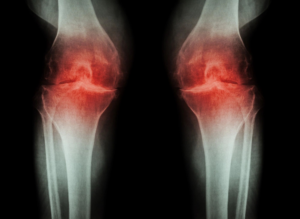

Ревматоїдний артрит: перші симптоми та сучасне лікування21.04.2026

Меновазан, Меновазан Саліцилат